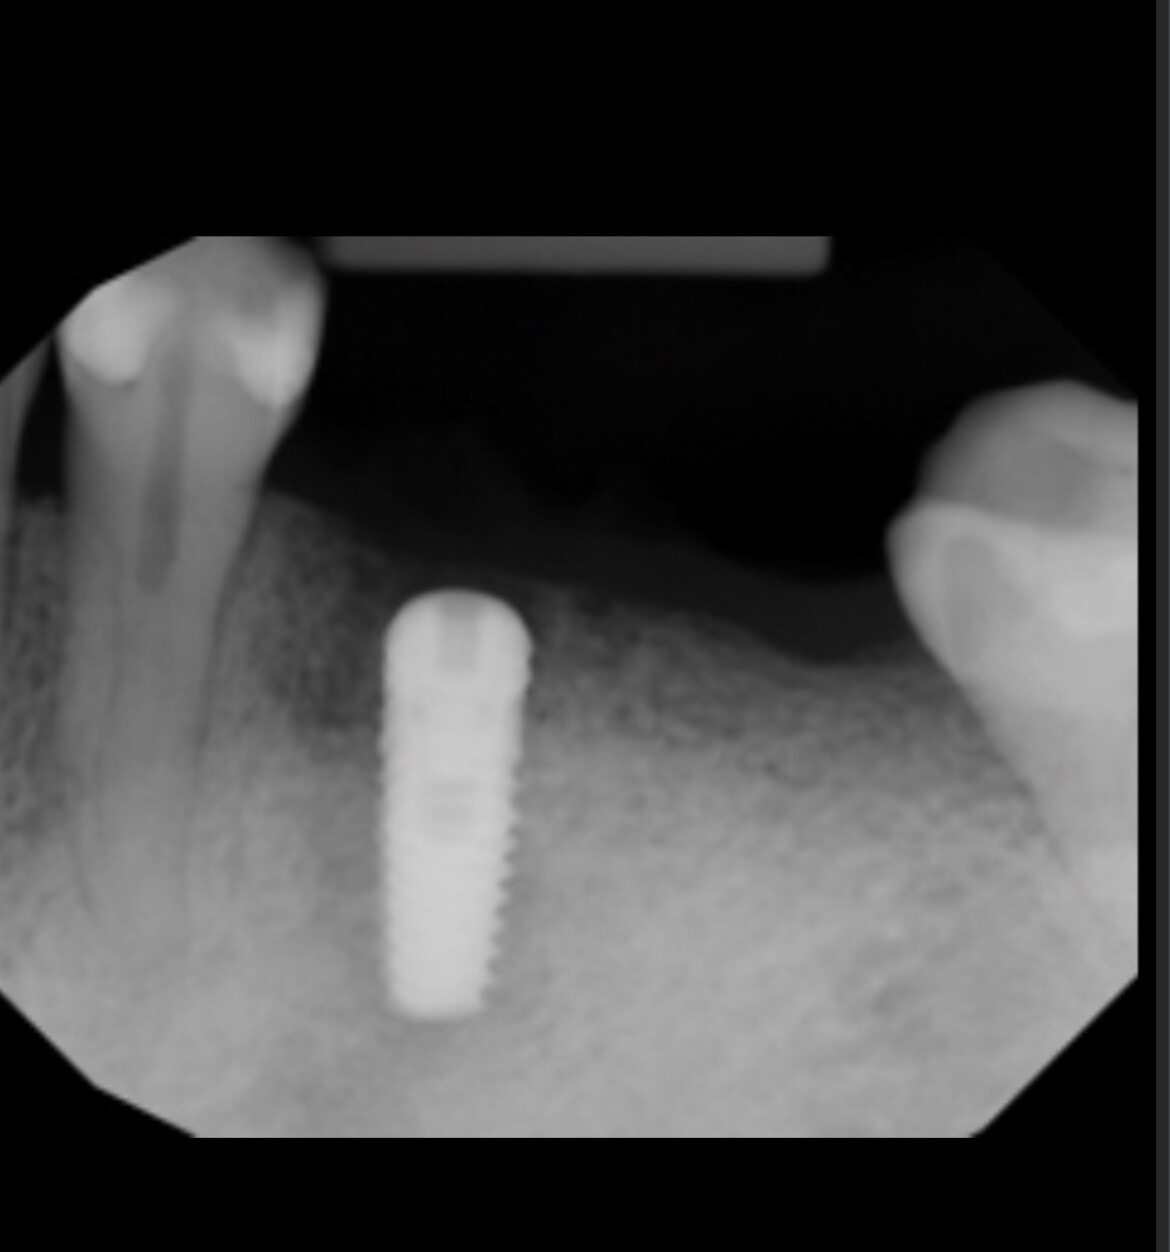

Implants placed too close: Is this restorable?

I am feeling really humble. I’ve placed multiple implants and thinking this should be a straightforward case. I was wrong. I know it’s poorly planned and freehand did not go well. Are these restorable? Should I explant and redo? If I do remove these, how easy is it to remove these?